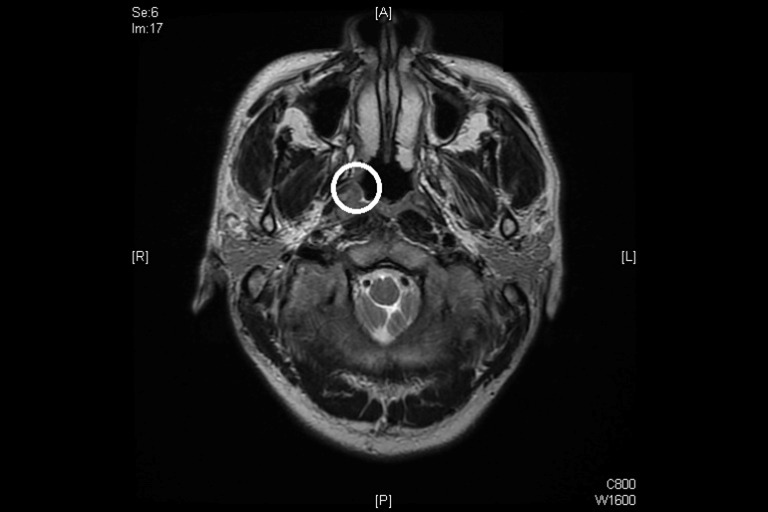

鼻咽癌影像照片(白色圓圈部位)。(圖片來源/彰基體系媒體新聞中心)

洪雲聰醫師日前收治一名30多歲的工程師;依據工程師述說,年輕時偶爾會流鼻血,通常鼻子壓個20分鐘,血就止住了,但此次流鼻血症狀卻持續一週,因此非常警覺的到醫院求診。洪醫師為他進行鼻腔檢查,並未發現異狀,但在鼻咽內視鏡檢查時,卻發現鼻咽右側有兩顆腫瘤,經切片後確認為『鼻咽癌』,核磁共振造影檢查也顯示咽後淋巴結轉移。